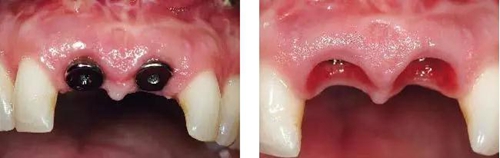

圖11、穿黏膜愈合1周后,牙齦外形良好。

圖12、種植體植入后2個(gè)月取出愈合帽,可見(jiàn)牙齦外形和齦乳頭維持得相當(dāng)好。

圖13、安放全瓷基臺(tái)。

圖14、最終修復(fù)體就位,冠頸部較窄。沒(méi)有任何牙齦和牙齦乳頭的退縮。

圖15、種植體植入后12個(gè)月的微笑相。